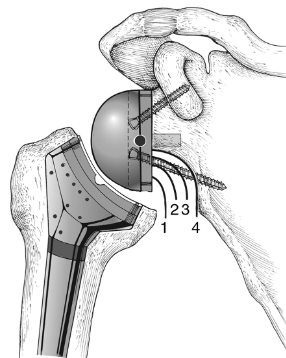

고관절 치환술(Total Hip Arthroplasty)

적응증: 고관절 치환술은 고관절 골관절염, 류마티스 관절염, 무혈성 괴사 또는 고관절 골절이 있는 개인에게 일반적으로 수행됩니다.

절차: 고관절 치환술 중 손상된 고관절의 볼-소켓 구성 요소를 인공 부품으로 교체합니다. 이 절차는 다양한 수술적 접근법을 사용하여 수행될 수 있습니다.

혜택: 고관절 치환술은 통증을 완화하고 고관절 기능을 회복하며 환자가 독립성과 이동성을 회복할 수 있도록 해줍니다.

- 임플란트 배치: 보철 관절 표면을 포함한 인공 관절 구성 요소는 시멘트 또는 압입 기술과 같은 특수 재료를 사용하여 제자리에 고정됩니다.